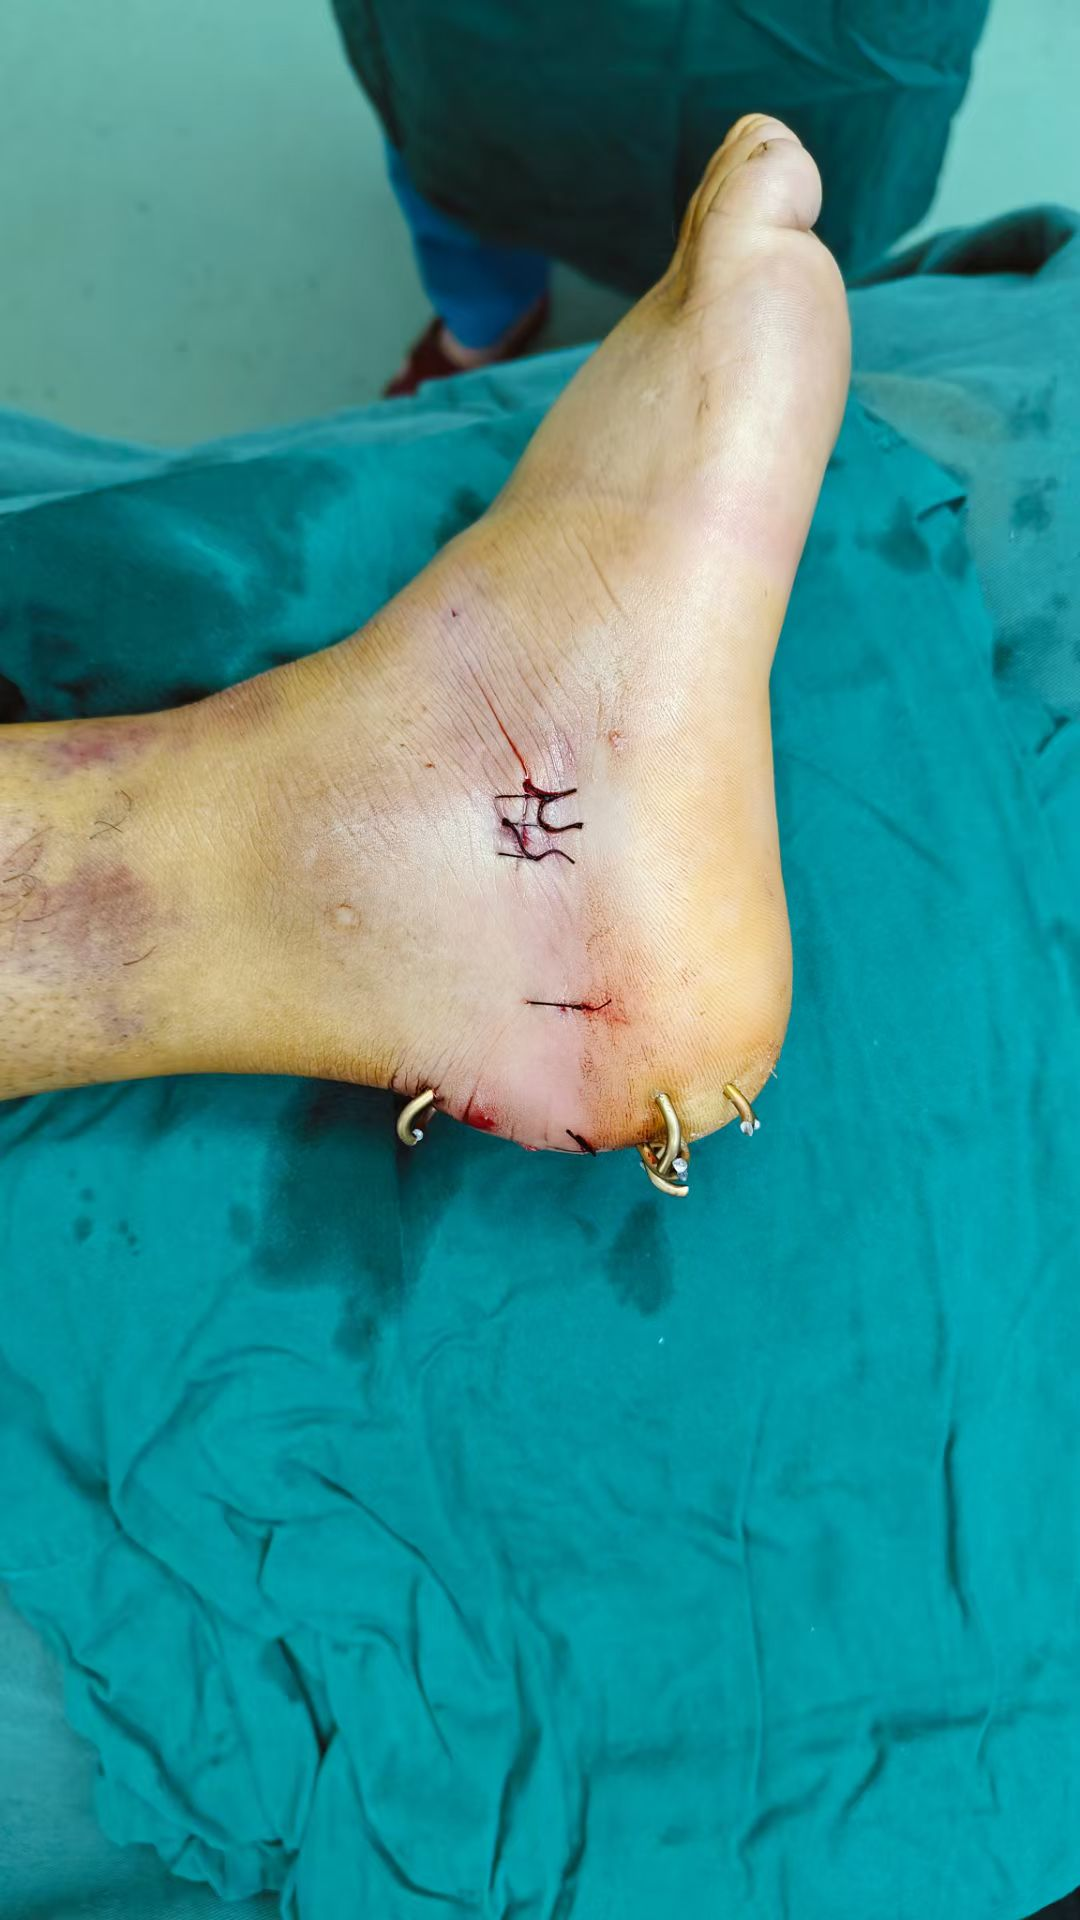

图片图片图片

跟骨粉碎性骨折闭合复位微创经皮穿针内固定